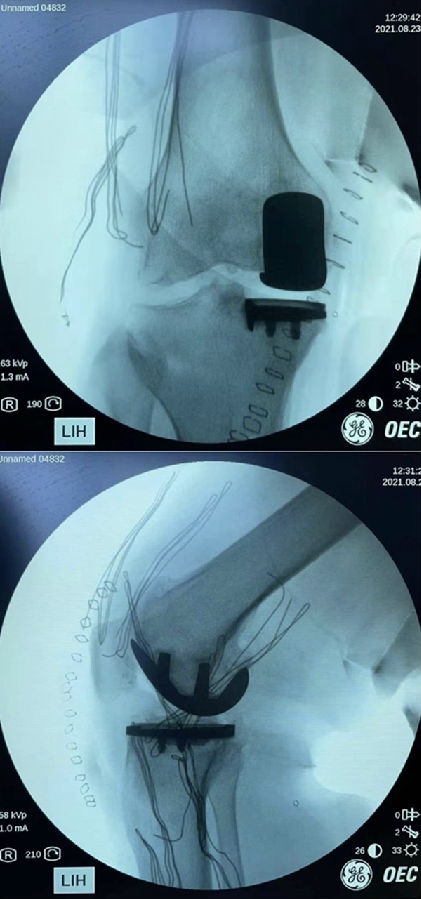

术后